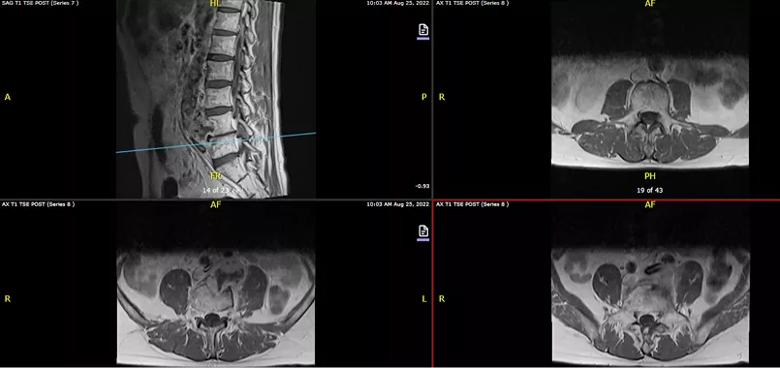

Figure 2. Sagittal and axial T1 MRI revealing a retroperitoneal mass invading the L4 vertebral body, abutting the L3 and L5 vertebral bodies and displacing the common iliac artery and vein.